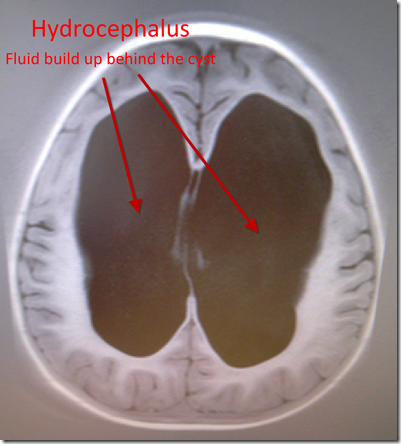

Figure: The Hydrocephalus - Fluid build up behind the cyst

Jenifer can’t give any guarantees that Kaiden’s gross motor skill will improve once the procedure has been completed as damage to those sections of his brain may already have been done, but she is confident based on previous cases that the outlook is good. At worst there should be no further exacerbation of the hydrocephalus and thus no more damage incurred. As Kaiden is so young it is difficult to tell what is late development due to damage and what is late development due to…well..being a lazy boy. In saying that she is very certain that being over six months behind in his gross motor skills is due to the hydrocephalus and the cyst.